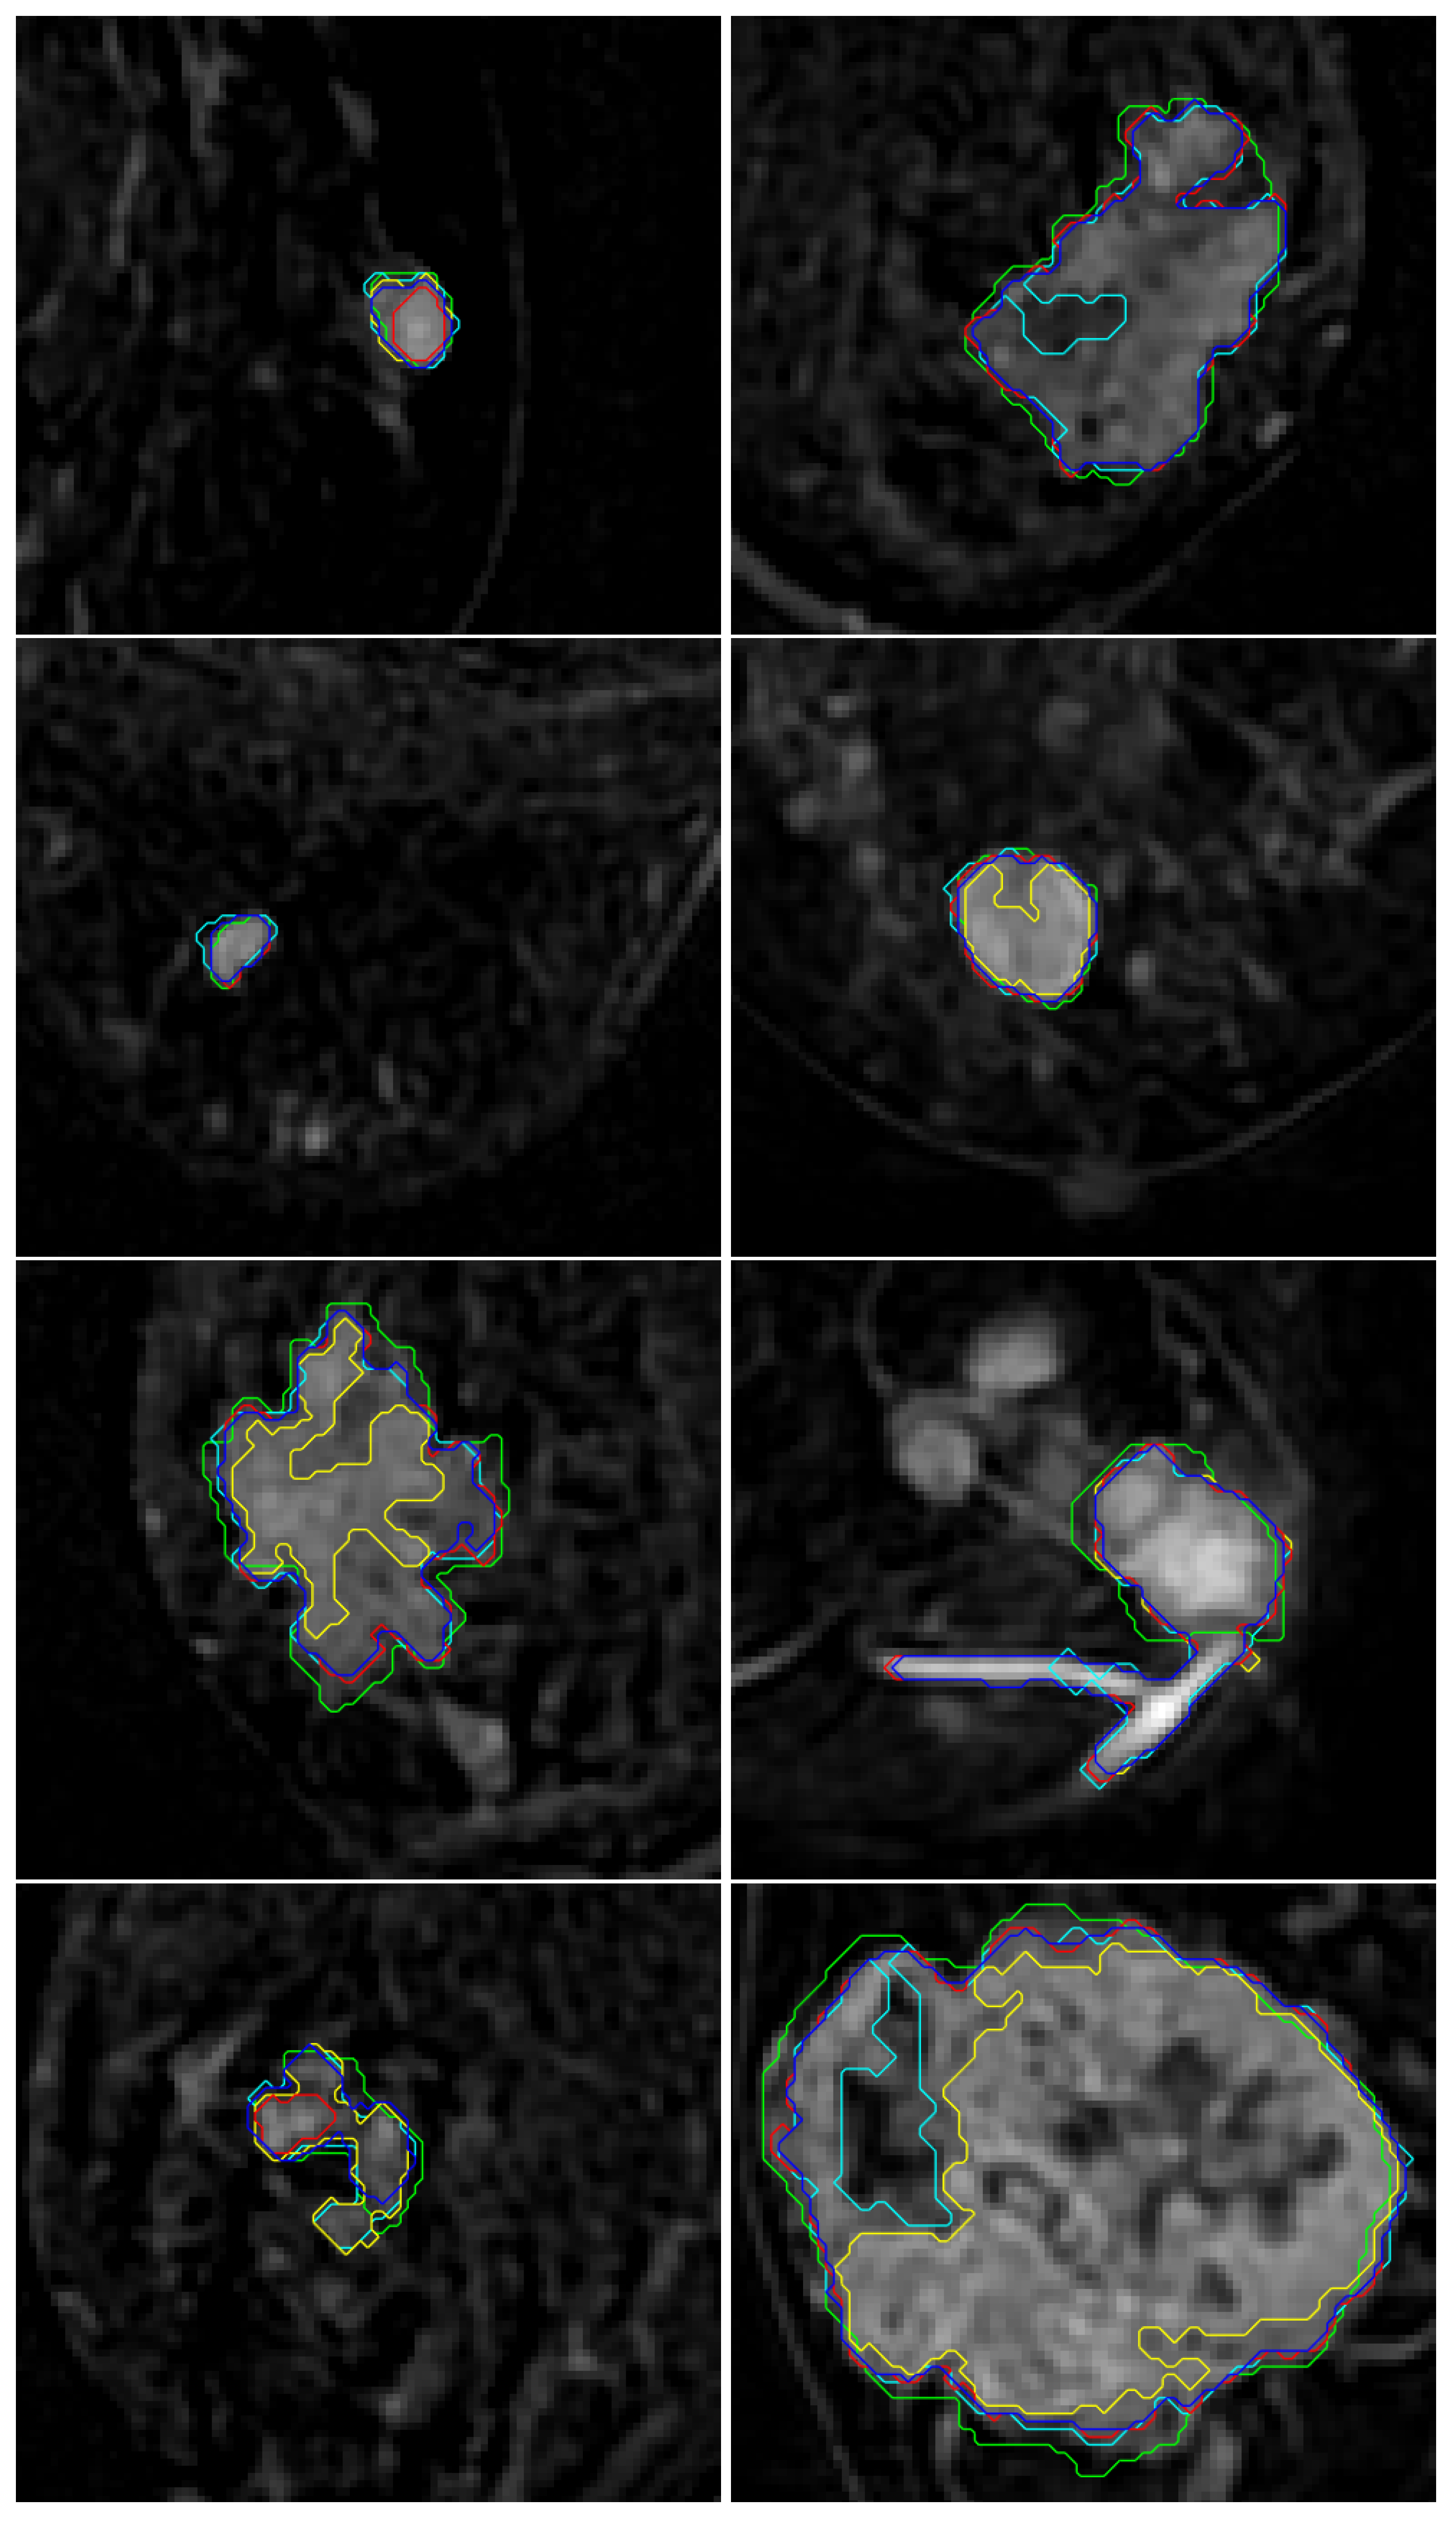

5.4.1. Case with Low Contrast-Enhanced Mass

5.4.2. Case with Blurred Boundary Mass

5.4.3. Case with Irregular Mass